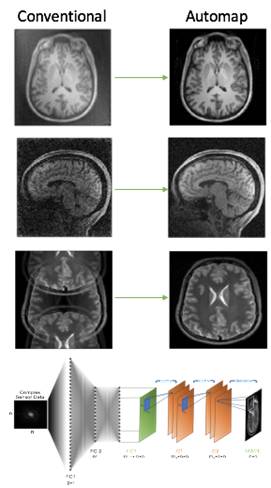

来自麻省总医院、A.A.Martinos生物医学成像中心和哈佛大学的研究人员开发了一种全新的名为“AUTOMAP”的图像重建深度学习框架。

传统的图像重建需要使用离散变换和各种过滤算法,并在实施时使用手动信号处理。而AUTOMAP 则使用统一的图像重建框架取代了这种方法,无需任何专家知识就可以学习传感器与图像域之间的重建关系。

左边为传统图像重建,右边为AUTOMAP新型框架。资料来源: https://arxiv.org/abs/1704.08841